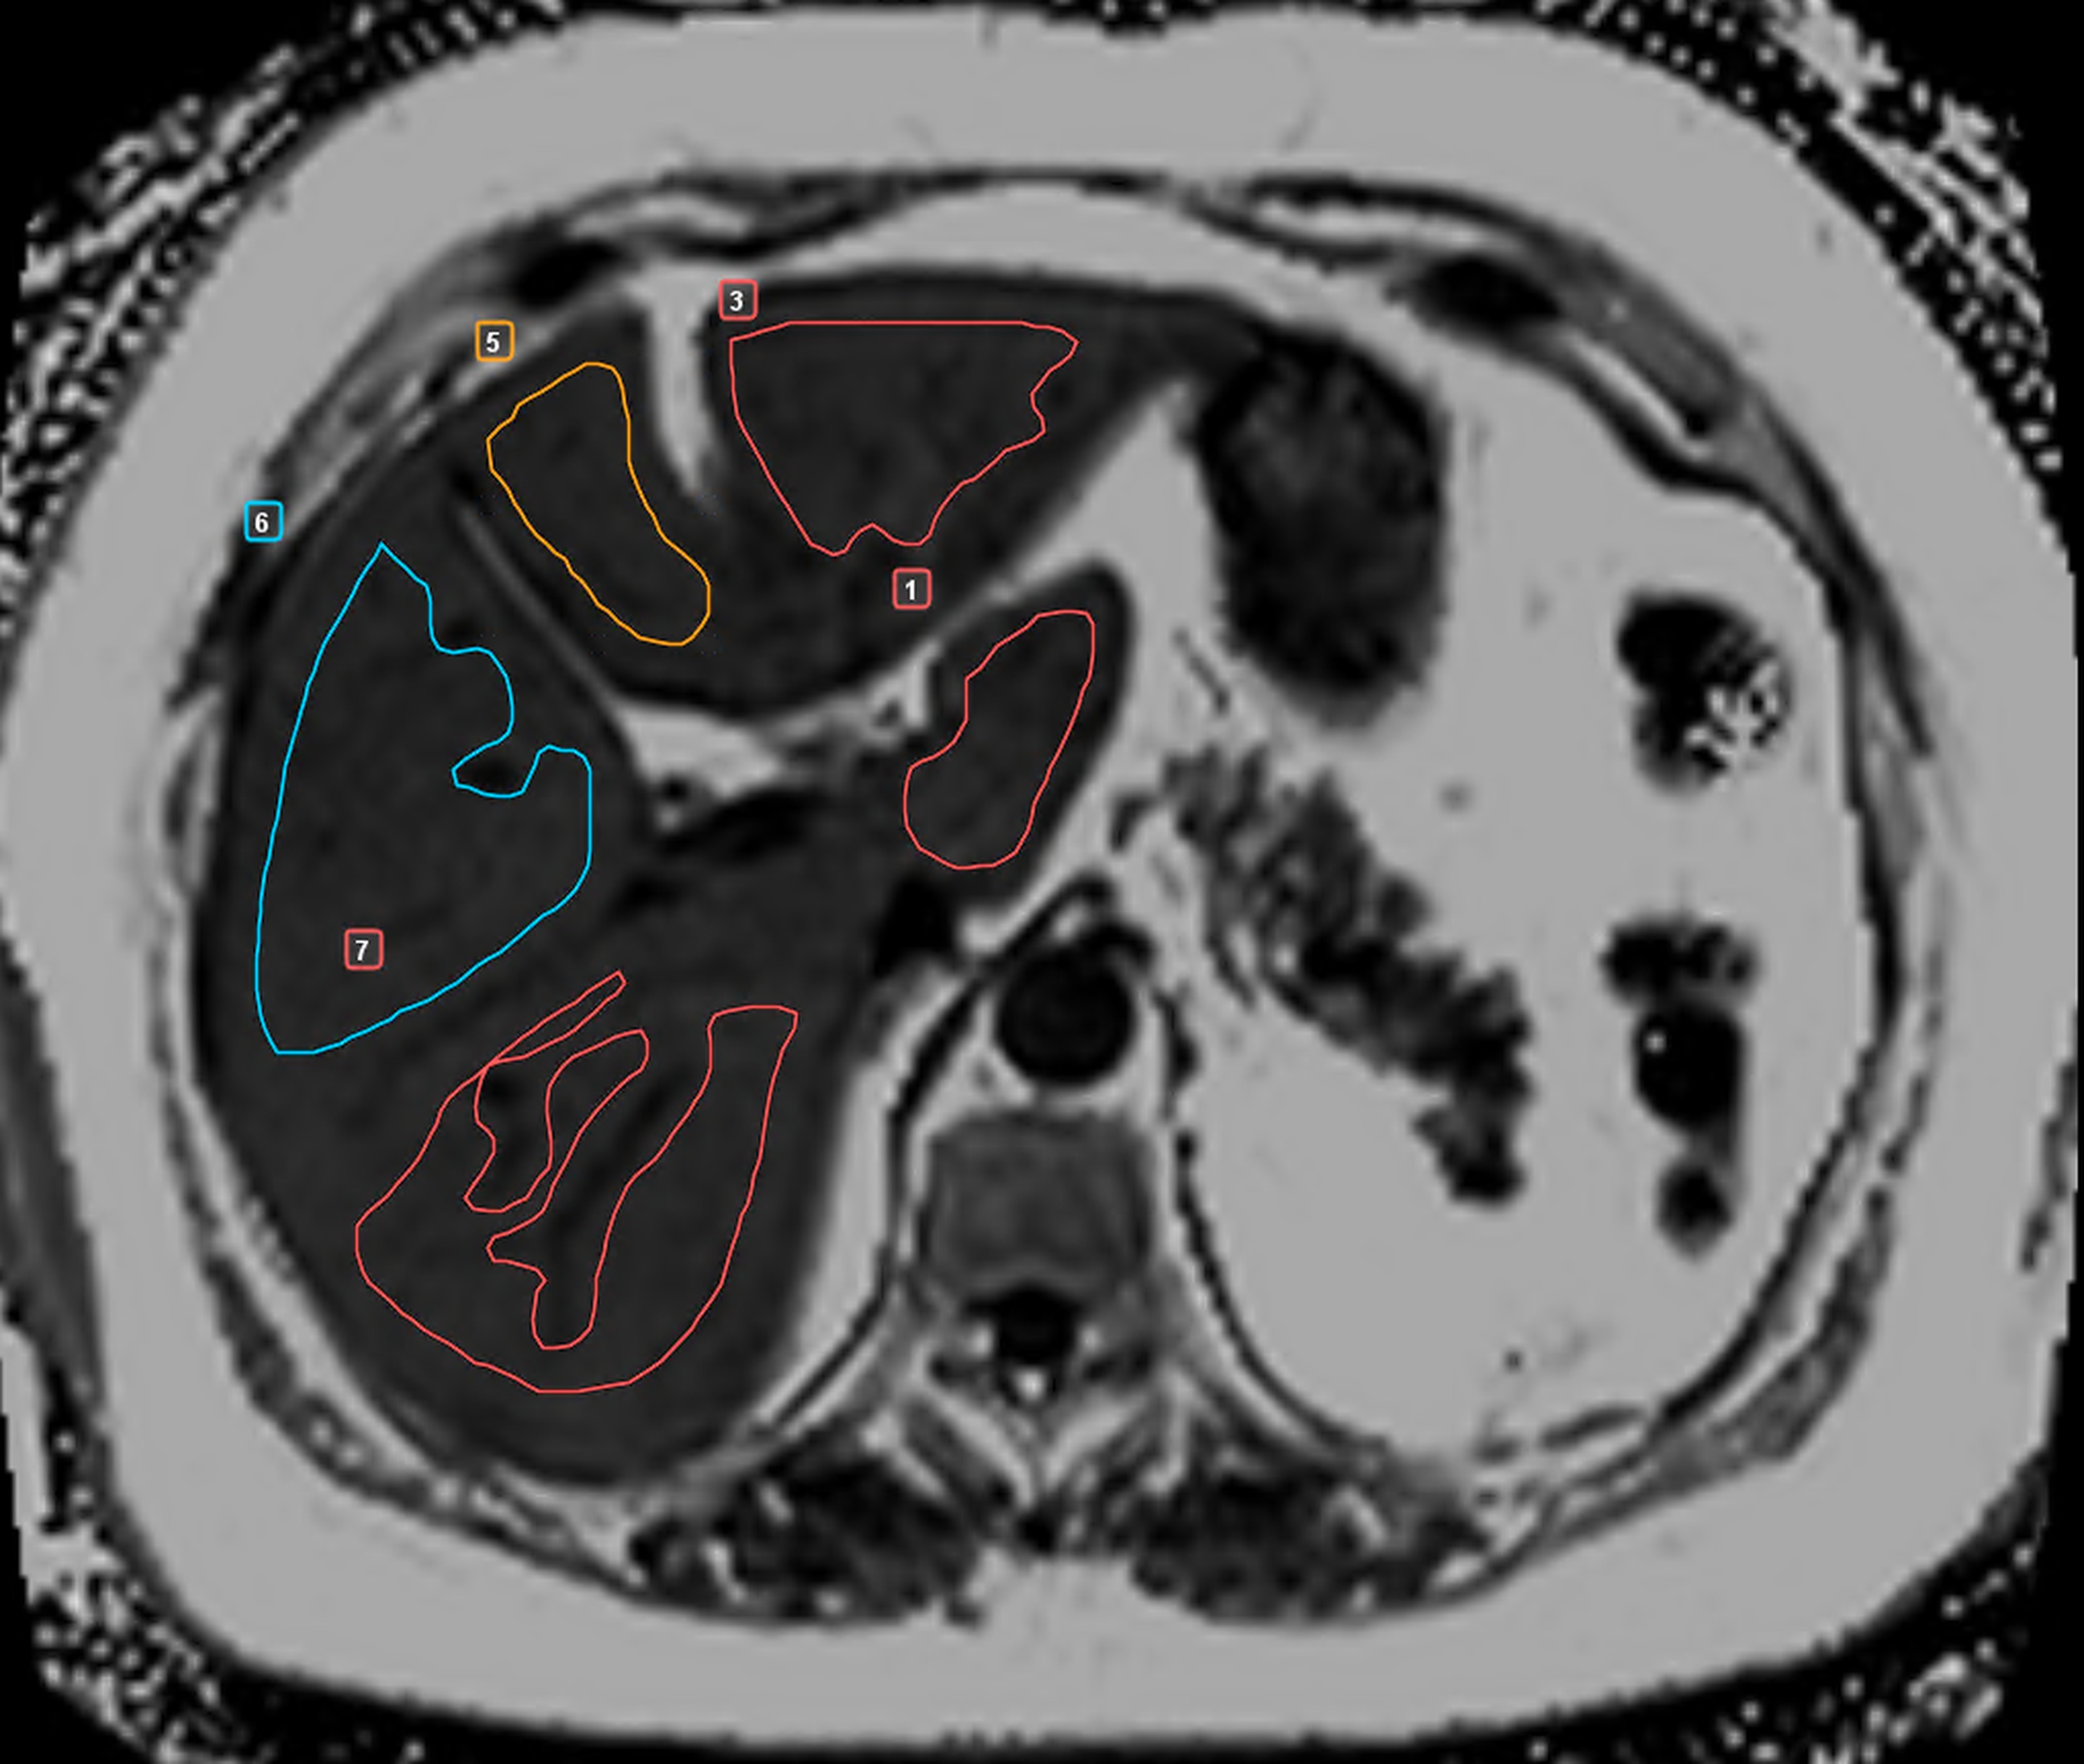

Сегментарный анализ осуществляли в соответствии с классификацией Couinaud. В каждом сегменте на аксиальных изображениях формировали зоны интереса максимальной площади с исключением сосудов, желчных протоков, очаговых образований и субкапсулярных участков (рис. 1).

Рисунок 1 - Пример измерений протонной плотности жировой фракции в S1, S3, S4b, S5 и S6 печени